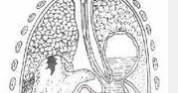

• 胸膜疾病

胸膜疾病是對(duì)胸膜發(fā)生疾病的概括, 胸膜是一層菲薄半透明的膜樣結(jié)構(gòu)覆蓋在胸壁內(nèi)面及肺和縱隔的表面,其中覆蓋于肺及膈表面的胸膜稱臟層胸膜,而被覆胸膜和縱隔臟器的一層...